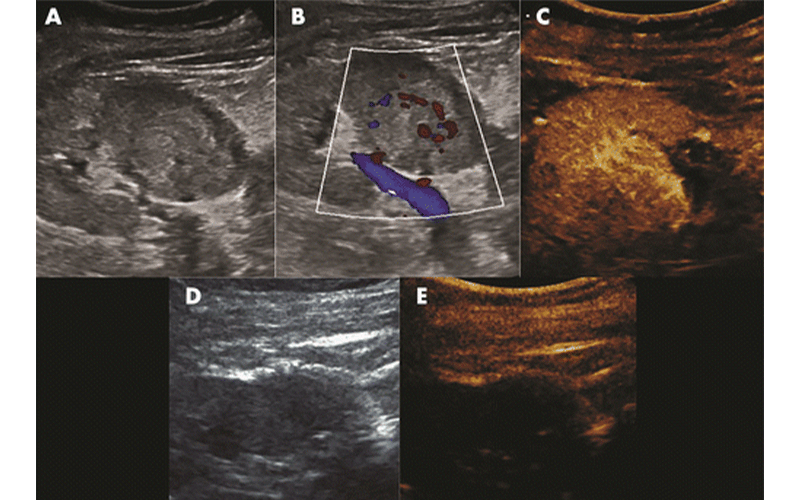

US appearance of renal cell carcinoma in a 61-year-old woman. A, Gray-scale US image shows a hyperechoic, well-circumcised, 3.5-cm mass at the lower pole of the right kidney. B, Doppler US image demonstrates evidence of vascularization within the mass; C, contrast-enhanced US confirms tumor vascularization; D, real-time gray-scale US image immediately after microwave ablation shows areas of gas with possible residual echogenicity; E, real-time contrast-enhanced US image shows no residual enhancing material in the ablation bed, confirming treatment effect. Joe et al, Radiology: Imaging Cancer 2019 ©RSNA 2019

Newer imaging modalities such as dual-energy CT can provide a more thorough evaluation of renal masses before a procedure, while techniques such as contrast-enhanced ultrasound (US) can monitor the ablative zone during the procedure in real time. The review discusses the benefits and limitations of US, CT, MR and PET imaging for diagnosis of RCC, as well as the utility of CT and US during ablation. For post-procedural and follow-up imaging, the review guides the reader through surveillance of the typical appearance of changes after ablation and describes signs of residual tumor and complications.